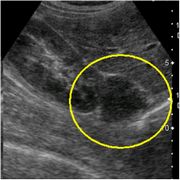

超音波画像